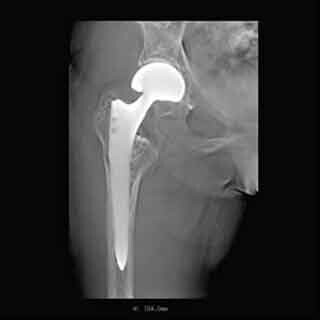

島津製作所は6月17日、同社X線TVシステム「SONIALVISION G4」向けに、金属アーチファクトを大幅に低減できる独自のトモシンセシスアプリケーション「T-smart」の販売を同日より開始すると発表した。

同製品は金属分離と逐次近似法を併用したトモシンセシス画像再構成方法を採用しており、従来法と比較して金属アーチファクトを大幅に低減することができる。金属の影響を受けずに骨の状態を把握できるため、人工関節置換術後の評価や骨折部の金属固定状態の経過観察に効果を発揮するとしている。